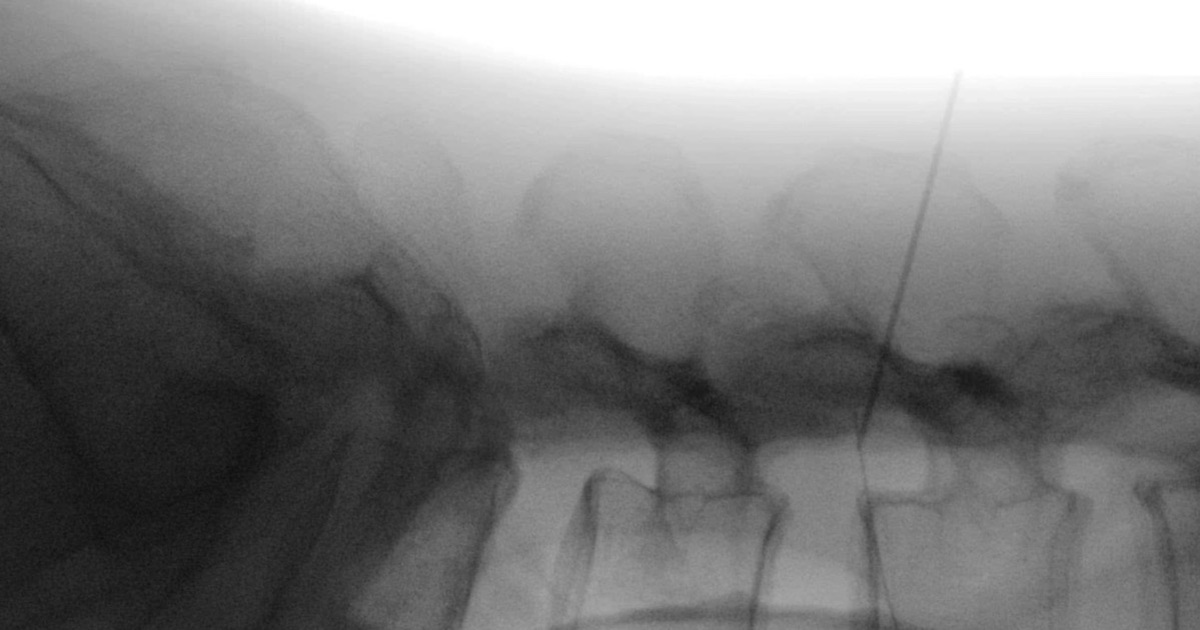

Qua thăm khám lâm sàng, các bác sĩ phát hiện nhiều nốt kim châm xung quanh vùng thắt lưng. Kết quả chụp X-quang phát hiện một dị vật kim khí cắm sâu theo chiều thân đốt sống.

Qua khai thác bệnh sử, bệnh nhân cho biết khi thấy đau ở vùng thắt lưng đã tự dùng kim châm cứu. Một đoạn kim châm dài 6cm đã bị gãy, đâm dọc vào đốt sống của bệnh nhân.

“Một phần của đoạn kim hướng cắm vào ổ bụng, rất may không làm tổn thương các tạng lân cận”, TS.BS Hoàng Thanh Tùng, Chủ nhiệm Khoa Chấn thương Chỉnh hình cột sống, Bệnh viện Quân y 103 cho biết, “Sau khi chụp chiếu và đánh giá, tầm soát các xét nghiệm đủ điều kiện phẫu thuật, chúng tôi đã tiến hành mổ lấy bỏ dị vật cho người bệnh”.

Sau ca phẫu thuật kéo dài 30 phút, các bác sĩ đã định vị chính xác vị trí, tiến hành lấy dị vật ra thuận lợi. Bệnh nhân phục hồi tốt, đi lại bình thường và đã được xuất viện.